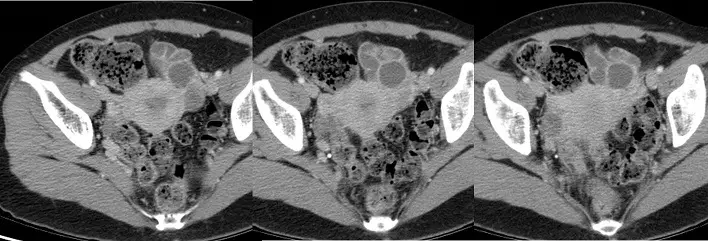

26歲女性病人,因下腹痛及發燒接受電腦斷層檢查(如附圖)。最可能之診斷為何? 圖片描述

CT 橫斷面顯示右側骨盆有一複雜囊性病灶:

1. 病灶為多房性(multiloculated)、囊腔內可見分隔(septations),壁明顯增厚並環狀增強。

2. 周圍骨盆脂肪組織呈散在條狀高密度(fat stranding),顯示局部炎症浸潤。

3. 病灶內未見脂肪密度(無 -100 至 -50 HU 範圍組織)或鈣化結構。

4. 臨床伴隨下腹痛與發燒,提示急性骨盆炎症。

以上所見符合輸卵管卵巢膿瘍在CT之典型表現:複雜、多房性囊性病灶、增強壁、周邊脂肪浸潤,同時伴有自由液或膿液(pyosalpinx)的成分 (radiology-test.fsm.northwestern.edu)。